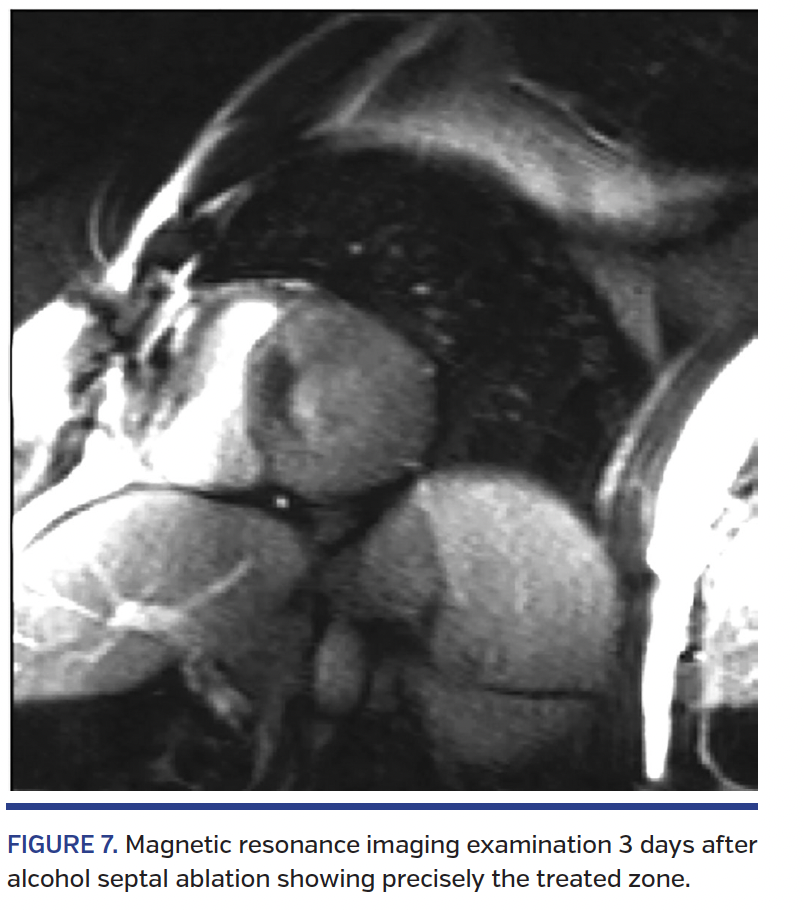

Long-term clinical outcomes. ASA has been associated with very promising long-term outcomes over the past few years (Figures 7 and 8). At our center, survival at 5 and 10 years was 94.1% and 86.9%, respectively, in a series of 240 patients with a mean age of 57 years. This represents a 1.3% mortality rate per year, which is comparable to that of the general French population matched for age and gender (Figure 9).10 The